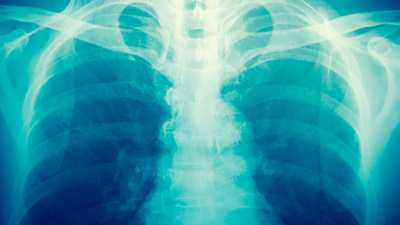

Nargilenin marpucunun içinde ve duvarında zamanla mikrop tabakası oluştuğunu belirten Savaşçı, şunları kaydetti: "Binlerce kişinin nefes alıp verdiği marpuç, birçok virüs, bakteri ve mantar için yaşam alanı oluşturur. Hijyeni sağlanamayan nargile, solunum yoluyla bir kişiden diğerine birçok hastalığı taşıyabilir. Ayrıca nargile tütününün nemi çeşitli mikroorganizmaların gelişimi ve büyümesi için uygun koşullar oluşturur.

Solunum yolu ile bulaşan grip ve zatürre gibi öldürücü sonuçlara neden olabilen virüsler nargile aracılığıyla birçok kişiye bulaşabilir. Verem hastalığına neden olan Mycobacterium Tuberculosis da nargile yoluyla bulaşabilen patojenlerden biridir."

Savaşçı, mantar enfeksiyonlarından ölümcül olabileni "İnvaziv Pulmoner Aspergillozun" nargile ile bulaştığına dair raporların olduğunu belirterek, "Tütün kaynaklı pek çok hastalıktan ve virüs salgınlarından korunmak için nargile kullanımından kaçınılmalı" dedi.